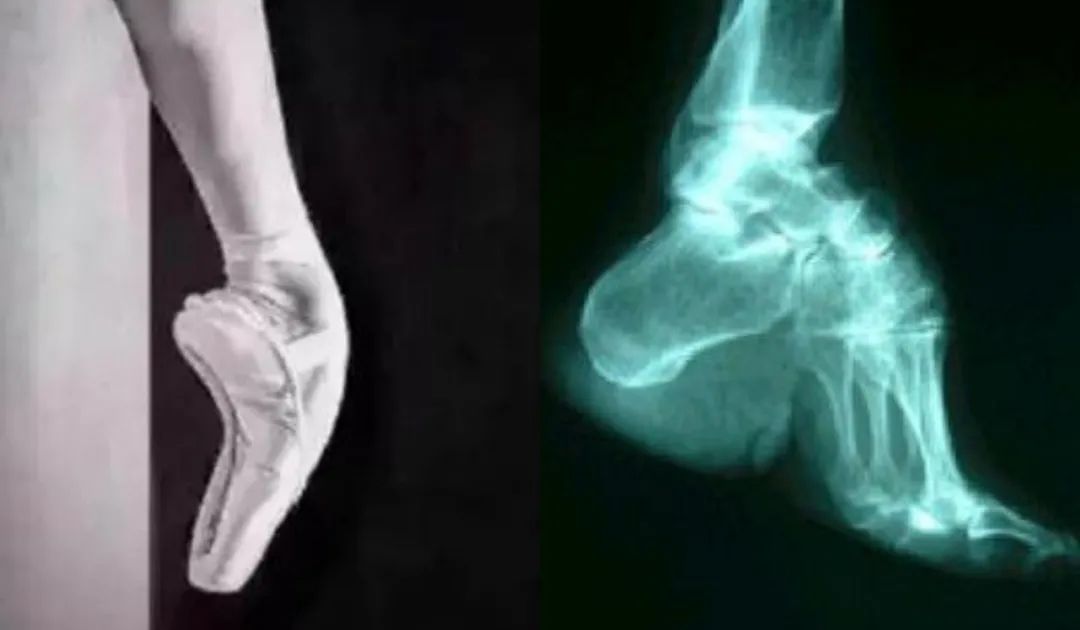

高脚背(左)与缠足X光片(右)对比